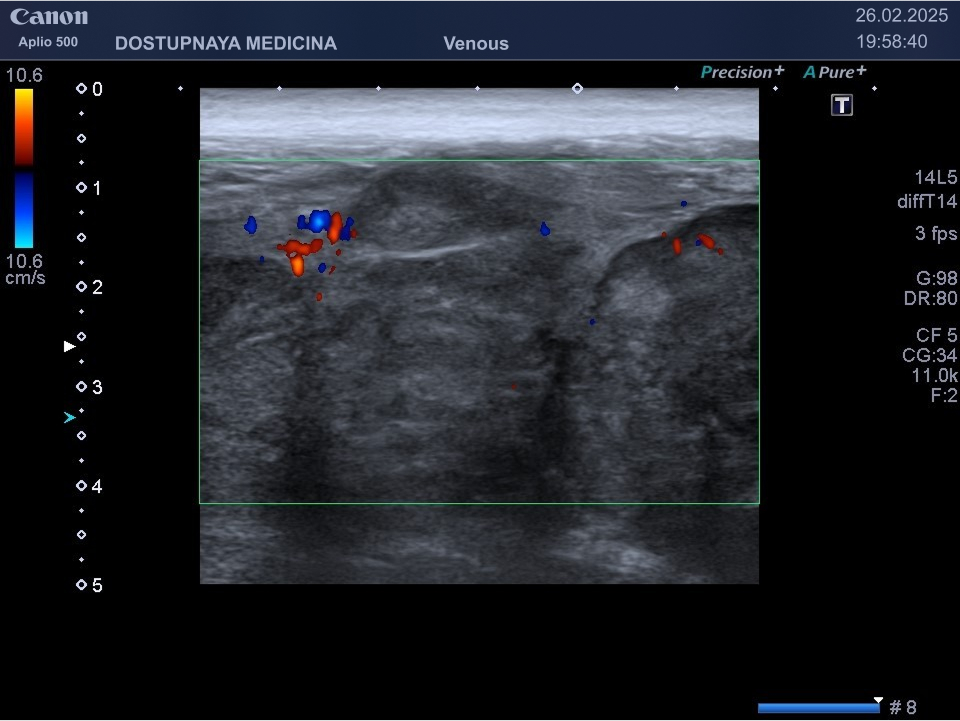

При ультразвуковом исследовании липома чаще всего выглядит, как гипоэхогенное образование овальной или округлой формы, мало отличающееся по своей эхоструктуре от окружающей её подкожной жировой клетчатки, без кровотока в режиме ЦДК. В описании заключения важно так же отметить прилежит ли близко опухоль к какому-либо кровеносному сосуду или нерву.

При ультразвуковом исследовании липосаркома чаще всего выглядит, как гипоэхогенное образование неправильной овальной формы, обычно с более пониженной эхогенностью (темнее) по сравнению с окружающей её подкожной жировой клетчаткой, с усиленным кровотоком в режиме ЦДК. В описании заключения важно так же отметить прилежит ли близко опухоль к какому-либо кровеносному сосуду или нерву.

Видно, что кровоток в образовании значительно усилен.